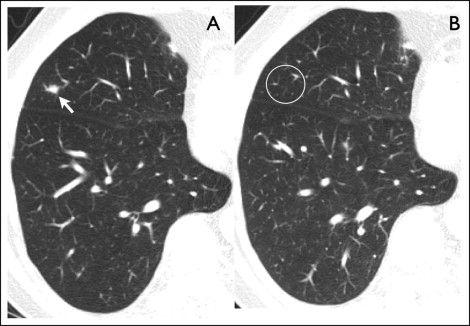

相关图片